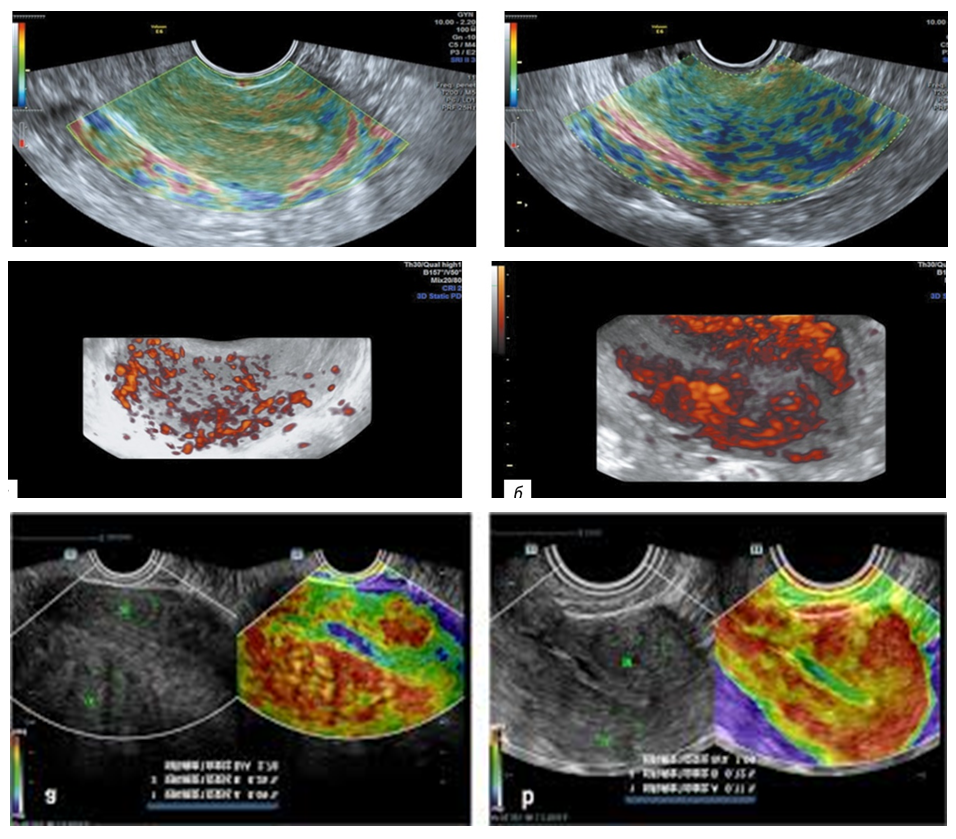

In adenomyosis, the myometrium was stained in shades of red in 83.3% of cases and shades of yellow in 8.3% of cases. Heterogeneous red staining was observed in 61.1% of cases, and heterogeneous staining in shades of red, yellow, and light blue was observed in 38.9% of cases (Fig. 3). | Figure 3. Patient K-va, 49 years old, file number 5453. Ultrasound image of diffuse adenomyosis |